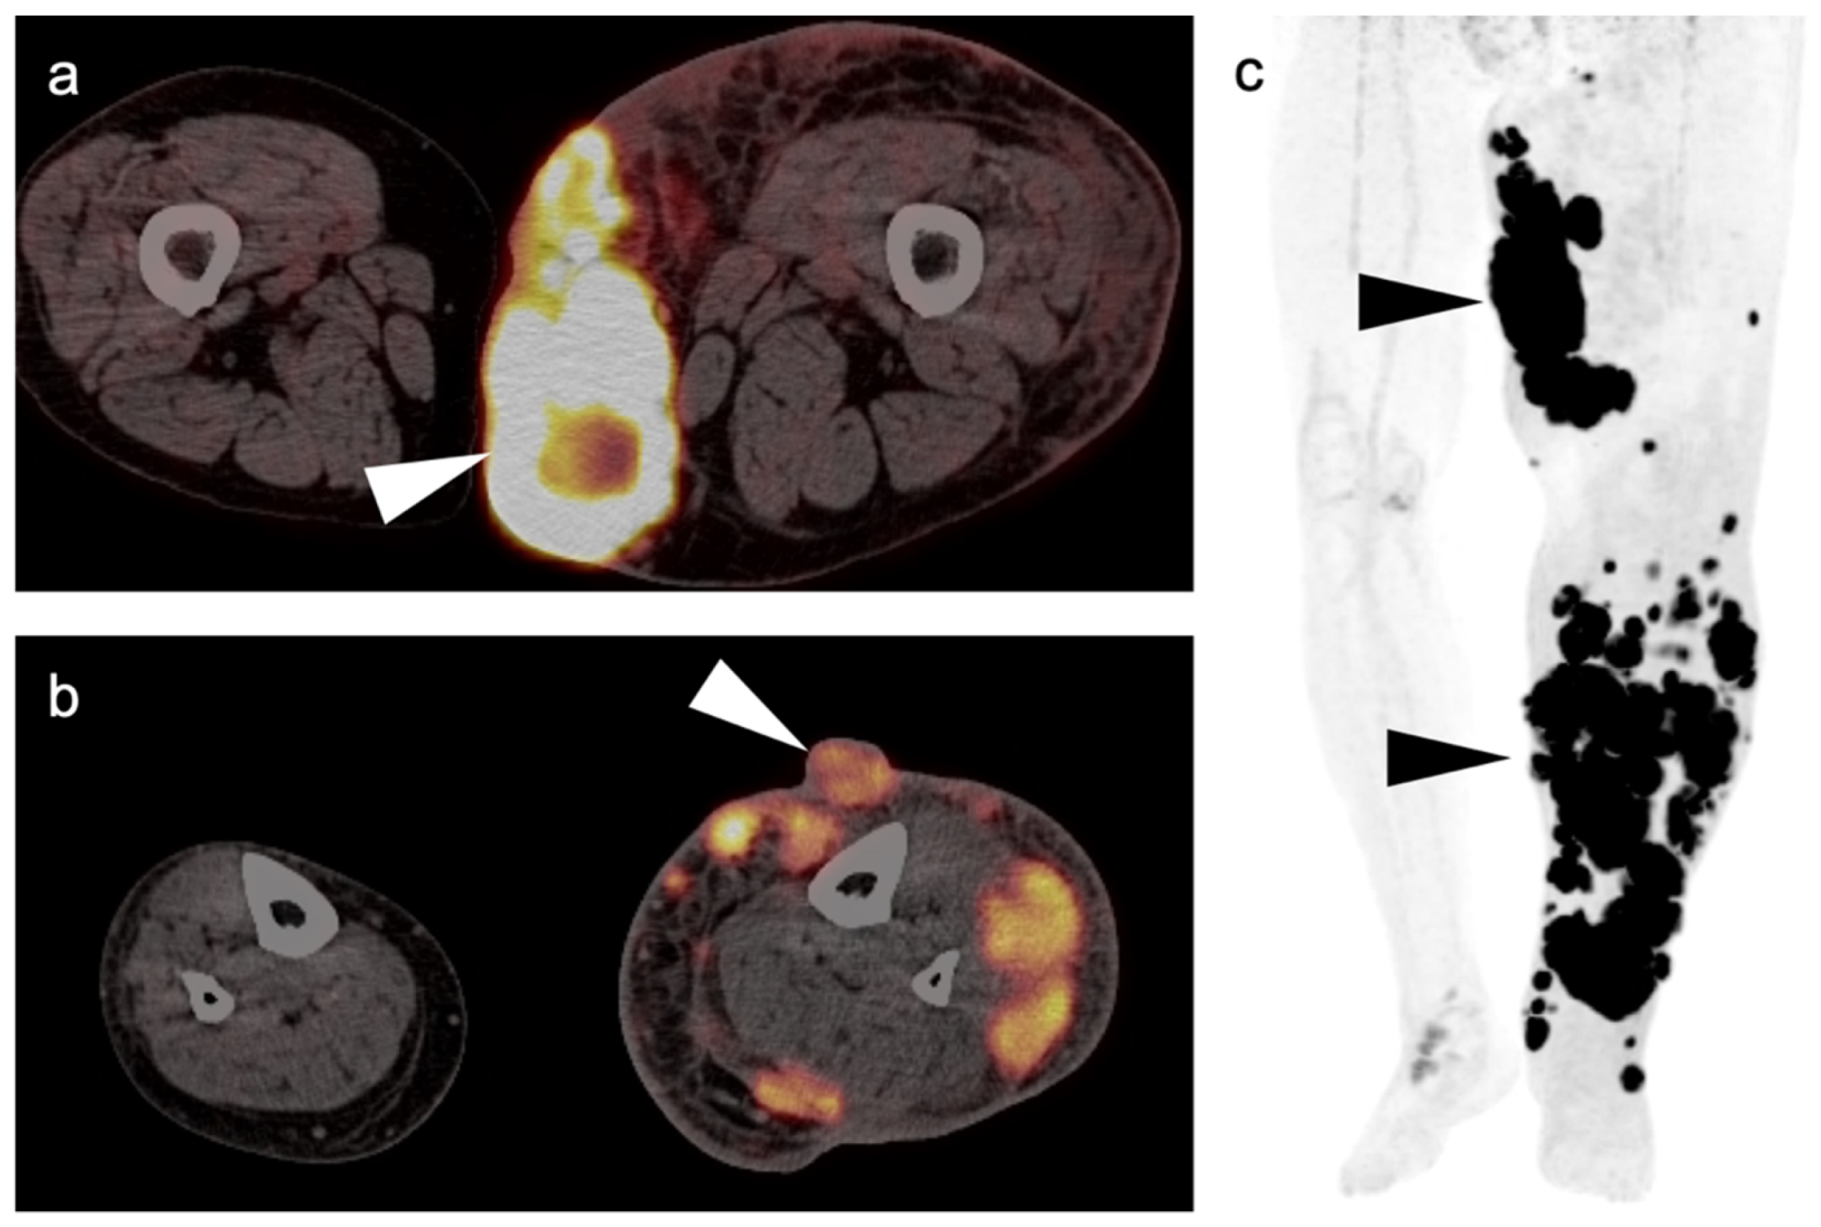

3.1.5. Rhabdomyosarcoma

3.1.6. Liposarcoma